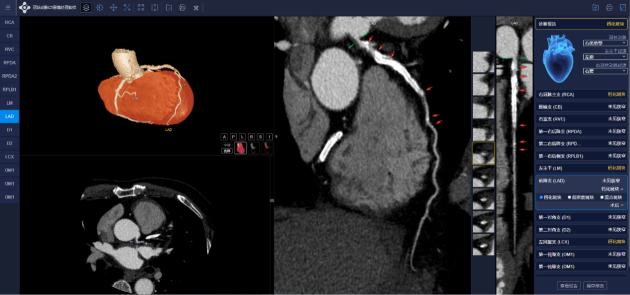

冠脉CTA智能分析系统产品界面 深挖诊疗逻辑,横纵交错开启多维产品矩阵 医准智能深耕横纵战略,横向覆盖每一个影像产品及设备。纵向从单部位、单病种出发到多部位、多病种覆盖,从影像诊断走向临床治疗,深挖患者诊疗逻辑,全面提升临床路径各个环节的质量与效率,横纵交错,为医生缔造全流程、智能化的AI整体解决方案。

医准智能冠脉CTA智能分析系统发布现场 日益增长的数据量及工作量冠脉诊疗亟需AI赋能 2020年国家心血管病中心发布的《中国心血管健康与疾病报告2019》显示,国内心血管病患者总人数已高达3.3亿,其中,冠心病患者数量超1100万人,患病率死亡率高居前列并仍在上升。在发现存在罹患冠心病的可能后,通常会选择冠脉影像学检查,通过解剖形态结果推测心肌缺血程度。其中高效、安全、无创的冠脉CTA检查更适合于大体量的门诊或体检筛查,目前已在临床得到广泛应用。 冠状动脉CTA检查需求日益增长随之带来的是影像医师及工作站无法满足临床对影像诊断高效、精准的要求以及医院管理规范化、报告标准化及精准医疗难以落地的现状,极大限制了影像科、临床科室,甚至是医院的发展,冠脉诊疗亟需AI赋能。 冠脉CTA智能分析系统全解析服务医生,高效聚焦患者 智能提取细小分支血管,减少心血管病变漏诊 医准智能冠脉CTA智能分析系统,可智能提取被其它冠脉AI产品忽略的细小分支血管,减少了所引起的严重心血管病变漏诊,对于术前手术规划亦有重要的临床意义和价值。 一键式智能分析与结构化报告,规范快捷 医生仅需一次点击即可进入AI界面,多模态图像及分析界面将同时显示,客户端界面右侧提供了极为丰富的冠脉诊断提示,涵盖了对目前临床常见解剖变异及狭窄斑块等病变的全面分析,并可一键式生成冠脉CTA结构化报告以及钙化积分报告,给到医生专业、规范、快捷的医学信息化服务。 多序列智能打印,优化临床胶片打印流程 系统支持一键自动智能排版、智能打印,可涵盖临床诊断所需的各角度VR及MIP、CPR等多序列的全面影像信息,极大的优化了胶片打印流程。